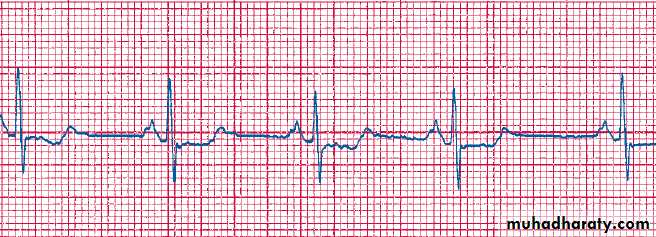

Ventricular Bigeminy

Normal

VPCVPC